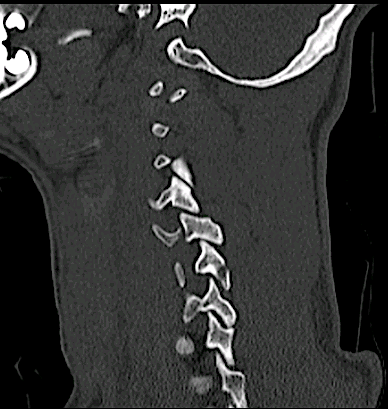

Obsérvese el hematoma prevertebral, la cifosis segmentaria y la afectación vertebral C4, C6 y C7.

El paciente presentaba tetraplejia nivel C4.

Los cortes sagitales demostraban una subluxación inestable en C4-C5 además del compromiso anterior C6-C7.